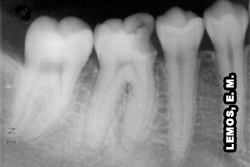

Salienta-se que, a inflamação pulpar não se evidencia através do exame radiográfico. A radiografia presta informações relativas às condições das estruturas dentárias e às eventuais modificações volumétricas e morfológicas da cavidade pulpar, e mostra ainda como se apresenta a região óssea do dente suspeito e dos vizinhos com relação aos aspectos periodontais e periapicais. Entretanto, nas fases avançadas do processo inflamatório pulpar é possível a identificação radiográfica de aumento do espaço pericementário do dente pulpítico decorrente da reabsorção cementária e óssea presente nesta fase do curso inflamatório. Para tanto, apenas a radiografia não constitui um exame capaz de firmar o diagnóstico da inflamação aguda, mas, bem avaliada, fornece dados que acrescidos às outras informações permitem esclarecer dúvidas, por vezes, facilitando o estabelecimento do diagnóstico clínico provável, sobretudo na fase irreversível, quando da identificação do dente envolvido. É necessário tornar relevante que, a radiografia é um exame auxiliar do diagnóstico. A radiografia possui as qualidades ilusórias de todas as sombras. Deve-se observar a presença de cáries, câmara pulpar, nódulos pulpares, o endodonto, qualidades das obturações endodônticas, fratura de instrumentos ou corpos estranhos, fraturas radiculares, reabsorções internas e externas e a existência de lesões radiolúcidas sugerindo necrose pulpar. |

Paciente apresenta dor irradiada nos pré-molares | Tratamento endodôntico insatisfatório no 36 (responsável). Observar sobreposição do forame mental no periápice do 34, podendo levar a uma falsa interpretação |

Lesões cariosas, inspecionar profundidade, exposição pulpar e associar com as características da dor, por meio dos recursos semiotécnicos para determinar o diagnóstico e tratamento adequado | Observar rarefações ósseas periapicais circunscritas no 12 e 22, rarefação óssea periapical difusa no 21 e aumento do espaço pericementário no 11 | Dente 46, observar a relação teto da câmara pulpar e assoalho, praticamente encostados, como forma de defesa da polpa, muita atenção no momento da cirurgia de acesso, pode levar à perfuração |